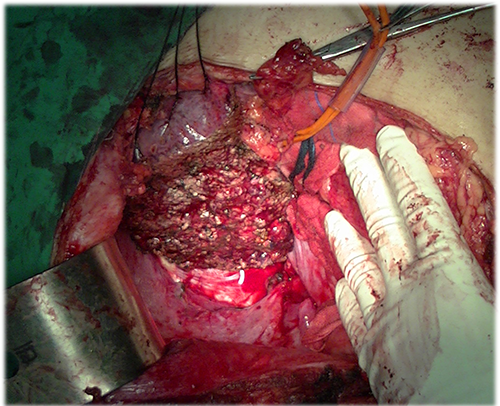

右肝癌----右肝部分切除